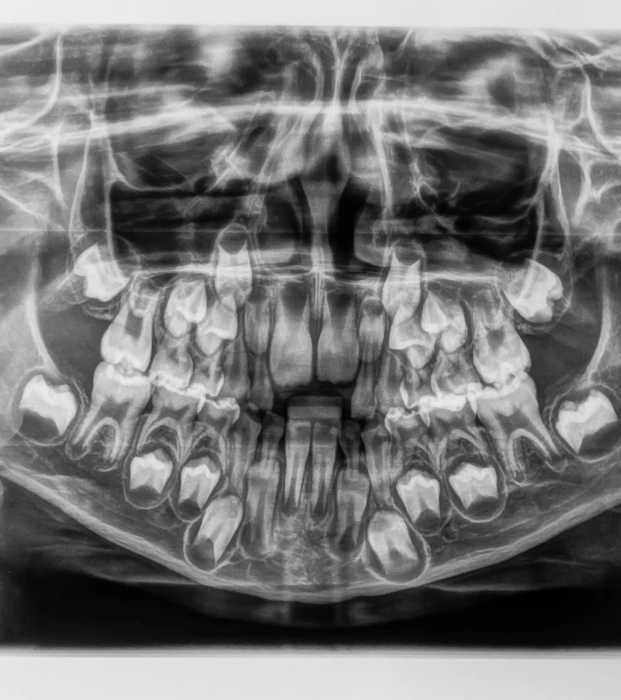

A Panorex is a state-of-the-art imaging tool that delivers a comprehensive view of your dental and skeletal structure, surpassing the capabilities of standard X-rays. During the procedure, you’ll sit comfortably with your chin resting on a small ledge while the machine rotates around your head, capturing a full 360-degree image of your teeth, sinuses, and bone structure.

This panoramic view is crucial for your dentist, as it aids in identifying a variety of issues, including structural problems, infections, and asymmetries. By assessing the entire structure of your head, we can ensure that everything is functioning properly and address any potential concerns.